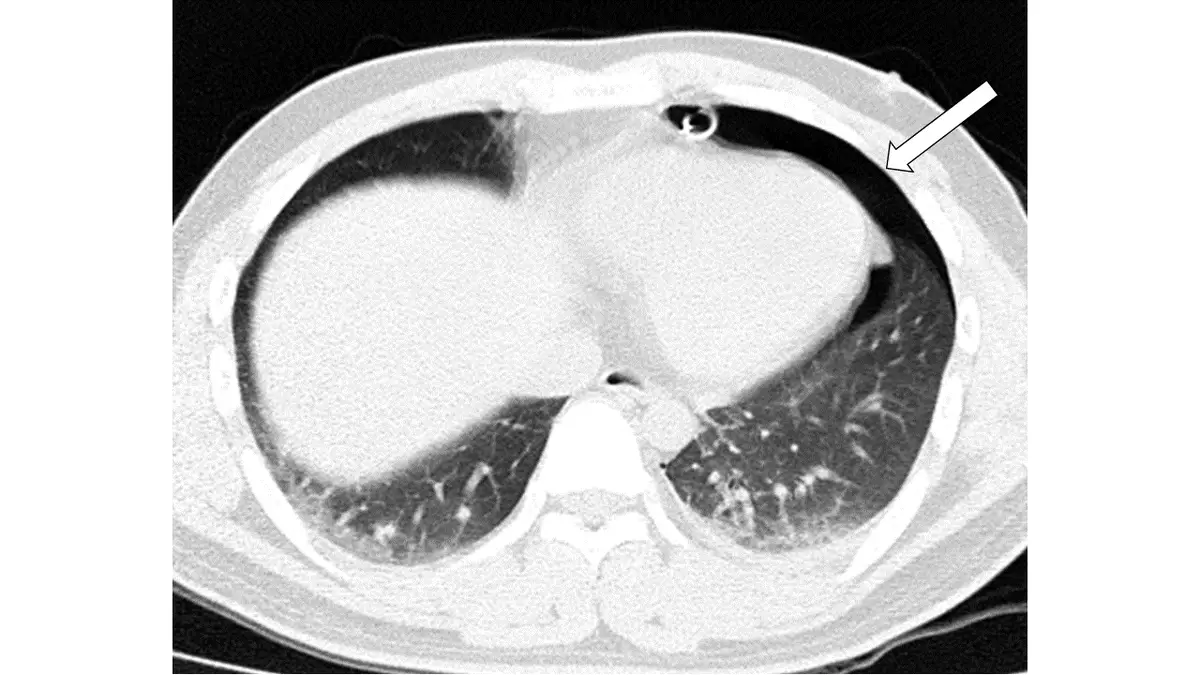

胸部外傷病人電腦斷層攝影呈現如下圖,有關箭號所指下列那一項最正確?

胸部外傷後電腦斷層(CT)影像辨識氣胸(pneumothorax)。氣胸是指空氣進入肋膜腔(pleural space),導致肺臟塌陷的狀態。在胸部外傷中,氣胸是僅次於肋骨骨折(rib fracture)最常見的併發症,約發生於半數胸部外傷病人。CT 對氣胸的偵測靈敏度遠高於傳統胸部 X 光,尤其是隱匿性氣胸(occult pneumothorax)。

本圖為胸部軸位 CT,肺窗(lung window)設定。影像中可見:

- 右側肺臟(影像左側):肺葉充氣良好,可見正常血管紋路(vascular markings)分布均勻,肋膜緊貼胸壁。

- 左側胸腔(影像右側):箭號所指處可見左側前外側肋膜腔內有大片黑色無血管紋路的空氣蓄積區,呈現典型「無肺紋帶狀區」。左肺受壓縮,肺組織被推向縱膈(mediastinum)側,影像中仍可見殘餘肺組織(含血管紋路)集中於中內側。

- CT 氣胸特徵:臟層肋膜(visceral pleura)與壁層肋膜(parietal pleura)之間出現游離氣體,該區域完全無肺血管影,此為氣胸的決定性影像表現。

- 箭號明確指向左側胸壁與肺邊緣之間的無回聲(低密度)空氣帶,符合氣胸診斷。